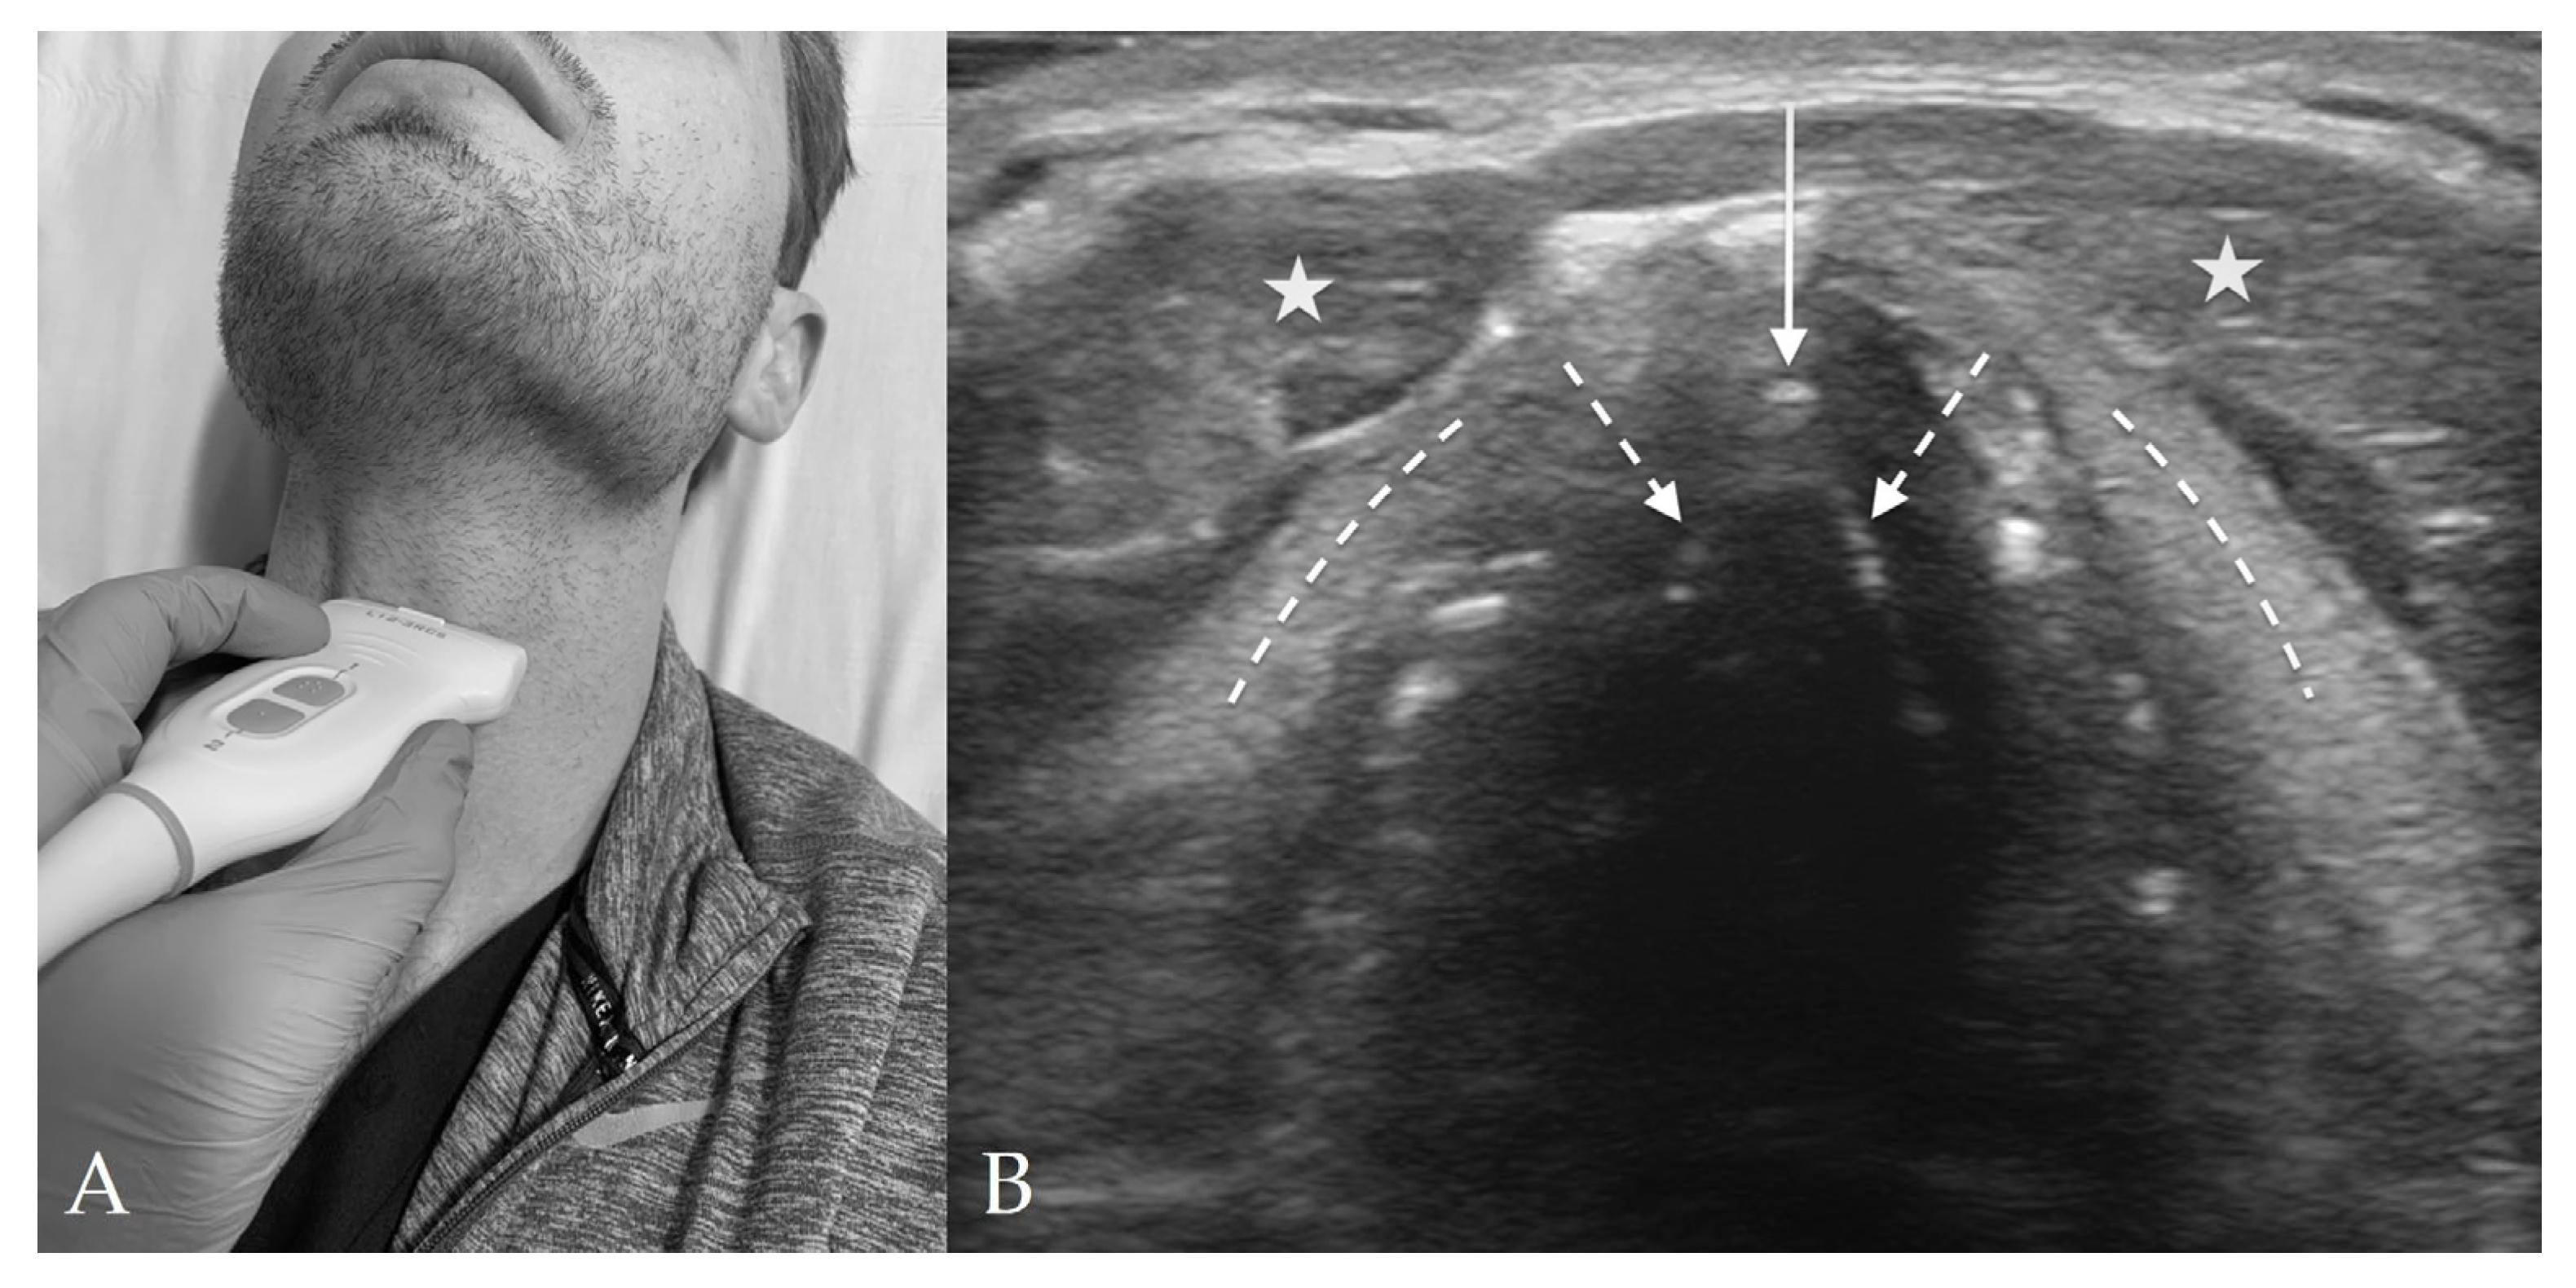

3. Probe Selection and Technique

4.4. Cricothyroid View

4.5. Suprasternal View

8. Preparation for Cricothyrotomy